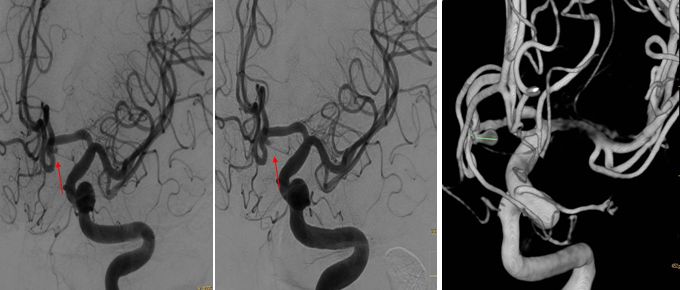

三次造影动脉瘤变化(相差三周时间)

2-13 —动脉瘤栓塞(瘤体明显增大)